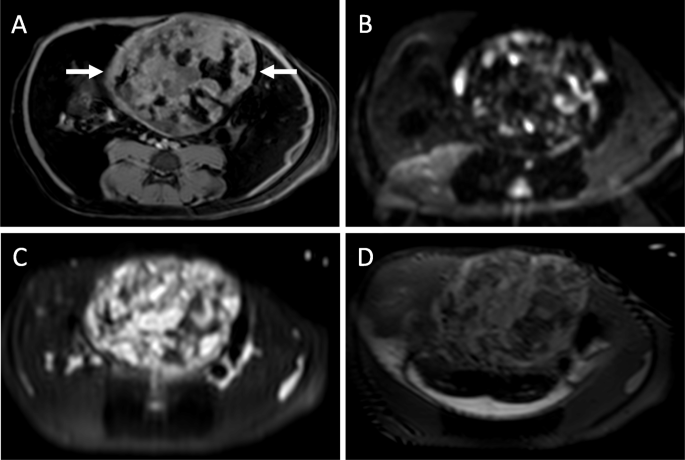

The scout images for the two CT examinations, separated by 5 weeks, showed a large calcified mass that was initially in the left abdomen measured as 5.7 × 3.5 cm (Fig. 1a) and subsequently in the right abdomen measured as 6.5 × 3.8 cm (Fig. 1b). On CT examination, the teratoma measured 6.6 × 4.8 × 4.7 cm and was well-circumscribed, predominantly solid, and heterogenous with soft tissue, fat, and areas of dense calcification (Fig. 1c, d). No fat-fluid levels were identified. Two HCCs were present, one with heterogenous enhancement and necrotic regions. Unlike the enhancement of the HCC after contrast administration, the teratoma did not enhance. The right uterine horn could be traced from the body of the uterus to the mass while the left uterine horn was coiled in the caudal abdomen and pelvis. On ultrasound, the tumor was solid with heterogeneous echogenicity, reflecting the fat content and areas of calcification with acoustic shadowing. Sonolucent areas were present that may have represented cysts. There was little vascularity on color Doppler imaging (Fig. 2). On T1-weighted THRIVE MRI, there was heterogeneously increased signal with areas of signal void representing fat. DWI showed some regions with increased signal. T2-weighted TSE indicated heterogenous hyperintensity while T2-weighted VISTA showed heterogeneous low signal intensity (Fig. 3).

Magnetic Resonance Imaging. a THRIVE image of the teratoma (arrows) with heterogeneously increased signal. Signal voids in the teratoma represent fat on this fat-suppressed imaging sequence. b Diffusion-weighted image with focal areas of increased signal. c T2-weighted TSE image with heterogeneous hyperintensity. d T2-weighted VISTA image with heterogeneous low signal intensity